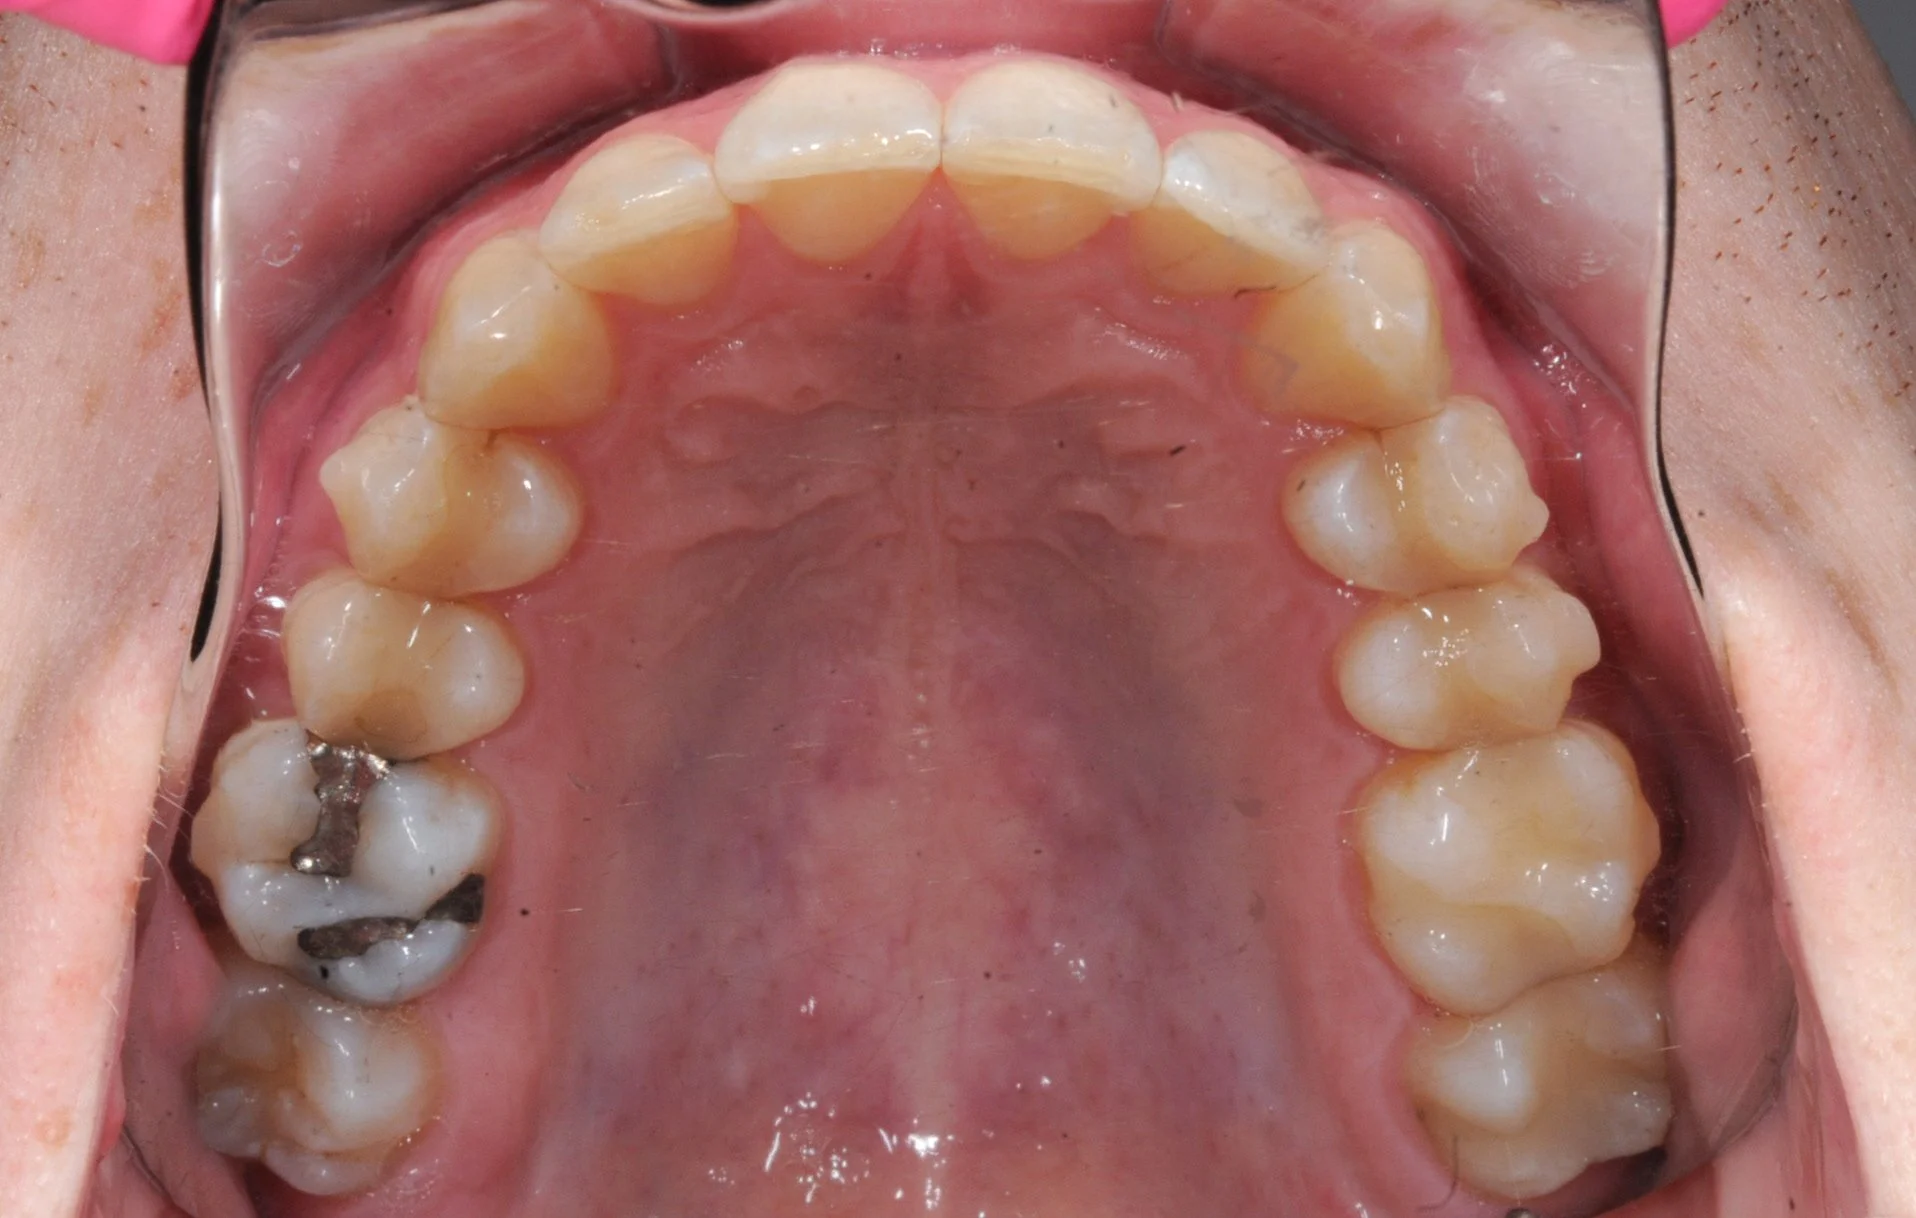

Orthodontics is about more than just straightening teeth—it’s about crafting healthy, functional, and beautiful smiles that last a lifetime. This patient came to us seeking a solution for the significant crowding in his lower teeth and minor upper crowding, all while prioritizing esthetic, invisible treatment options.

Significant crowding of the lower front teeth and some minor upper crowding brought this patient to us, seeking a discreet way to achieve straight teeth and an amazing smile. Like many of our patients, he preferred an esthetic solution that would minimize the visibility of orthodontic appliances during treatment.

We took our time to study the case and after talking through many of the treatment options Walker and Dr. Andrew determined that extracting a lower incisor was the best course of action. Extracting teeth is never a decision made lightly—in this case it was based on the significant crowding and the thin gingival tissue present. Attempting to align the lower teeth without reducing the number of teeth would have put the patient at a higher risk of developing gingival recession in the area.

To be as efficient as possible, we opted for a hybrid treatment plan tailored to his specific needs. For the upper teeth, clear aligners provided the invisible solution the patient preferred, while for the lower teeth, we selected Inbrace, a fixed appliance placed on the inside of the teeth. This combination offered excellent esthetics for the upper arch and the more predictable root control for the lower teeth needed to close the extraction space.